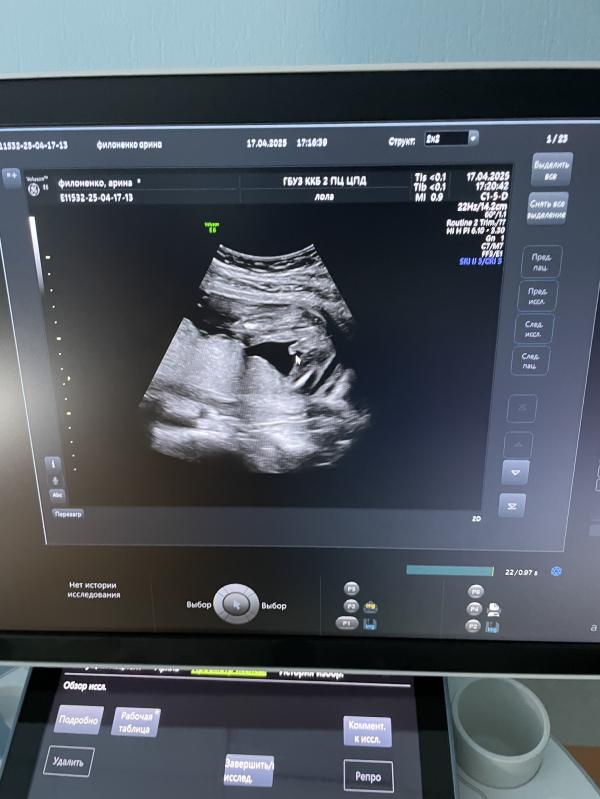

Второй скрининг)

На этот раз сходила на него в свою жк. На удивление врач узи оказалась очень хорошая, Лола Мария Алексеевна 🫶 Постоянно все комментировала, в конце показала снимки и разрешила пофоткать. Кто ходит в 5 жк, от души рекомендую)

У малышарика все хорошо, чуть отстает от срока по месячным (на 2 дня) - поставили 20+3, весит уже 360 грамм. Подтвердили мальчика 😁

Ну а у меня гипертонус, все как обычно, ничего нового… 🫠 Зато плацента чуть поднялась, в прошлый раз перекрывала зев 👍